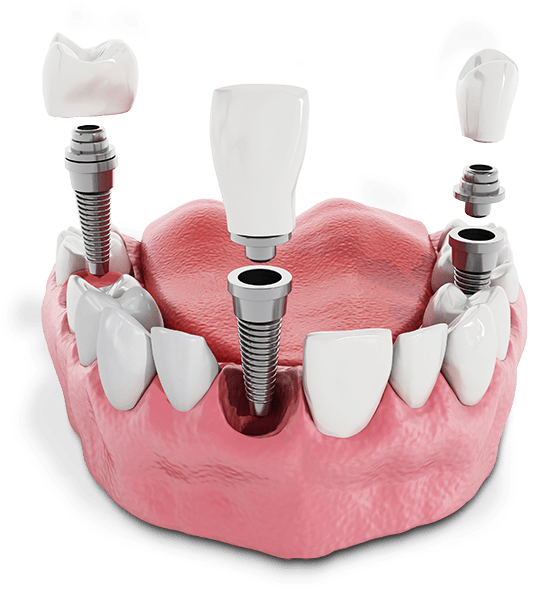

Article Contents Strategic Sourcing: Dental Implants Tijuana Cost Technical Specifications & Standards ROI Analysis & Profitability Importing from China: A Step-by-Step Guide Frequently Asked Questions Strategic Sourcing: Dental Implants Tijuana Cost Professional Dental Equipment Guide 2026: Executive Market Overview Professional Dental Equipment Guide 2026: Executive Market Overview Strategic Insight: The global dental implant market is […]

Article Contents Strategic Sourcing: Dental Implants Mexico Cost Technical Specifications & Standards ROI Analysis & Profitability Importing from China: A Step-by-Step Guide Frequently Asked Questions Strategic Sourcing: Dental Implants Mexico Cost Professional Dental Equipment Guide 2026: Executive Market Overview Dental Implants Mexico Cost Analysis Dental implants represent the cornerstone of modern digital dentistry, enabling precision-driven […]

Article Contents Strategic Sourcing: Dental Implants Las Vegas Prices Technical Specifications & Standards ROI Analysis & Profitability Importing from China: A Step-by-Step Guide Frequently Asked Questions Strategic Sourcing: Dental Implants Las Vegas Prices Dental Equipment Guide 2026: Executive Market Overview Dental Equipment Guide 2026: Executive Market Overview Dental Implants: Las Vegas Market Dynamics & Strategic […]

Article Contents Strategic Sourcing: Dental Implants In Turkey Price Technical Specifications & Standards ROI Analysis & Profitability Importing from China: A Step-by-Step Guide Frequently Asked Questions Strategic Sourcing: Dental Implants In Turkey Price Professional Dental Equipment Guide 2026: Dental Implants in Turkey Market Analysis Professional Dental Equipment Guide 2026: Executive Market Overview Dental Implants in […]

Article Contents Strategic Sourcing: Dental Implants Gps Cost Technical Specifications & Standards ROI Analysis & Profitability Importing from China: A Step-by-Step Guide Frequently Asked Questions Strategic Sourcing: Dental Implants Gps Cost Professional Dental Equipment Guide 2026: Executive Market Overview Professional Dental Equipment Guide 2026: Executive Market Overview Dental Implant GPS Systems: Cost Dynamics in Modern […]

Article Contents Strategic Sourcing: Dental Implants Florida Low Cost Technical Specifications & Standards ROI Analysis & Profitability Importing from China: A Step-by-Step Guide Frequently Asked Questions Strategic Sourcing: Dental Implants Florida Low Cost Professional Dental Equipment Guide 2026: Dental Implants Market Analysis Professional Dental Equipment Guide 2026: Executive Market Overview Dental Implants in Florida – […]

Article Contents Strategic Sourcing: Dental Implants Dallas Cost Technical Specifications & Standards ROI Analysis & Profitability Importing from China: A Step-by-Step Guide Frequently Asked Questions Strategic Sourcing: Dental Implants Dallas Cost Dental Equipment Guide 2026: Executive Market Overview Professional Dental Equipment Guide 2026: Executive Market Overview Dental Implants Cost Analysis & Strategic Procurement in the […]